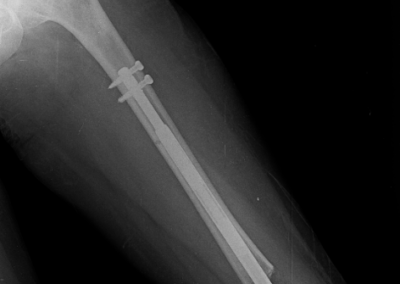

Lengthening SurgeryDec 30, 2021 | Case Examples Case 1: Tibiada Extension Over Nail (LON) Case 2: Femurda Extension Over Nail (LON Case 3: Femurda Automatic Nail Extension